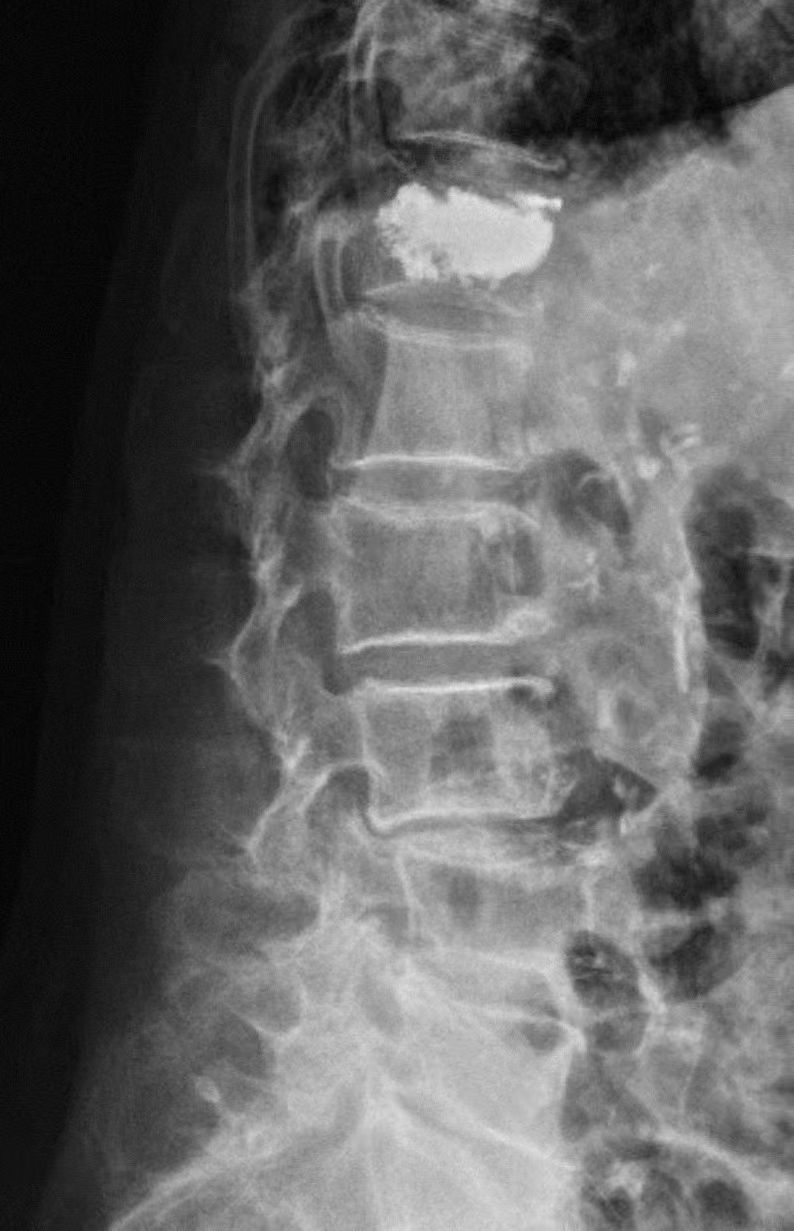

后经综合评估,刘奶奶选择了微创介入疗法——经皮椎骨成形术。术后,疼痛明显缓解,放射线检查提示骨折椎体骨水泥填充弥散良好。第二天,她在家人的搀扶以及腰围的保护下就能下地行走。

放射线检查提示骨折椎体骨水泥填充弥散良好。